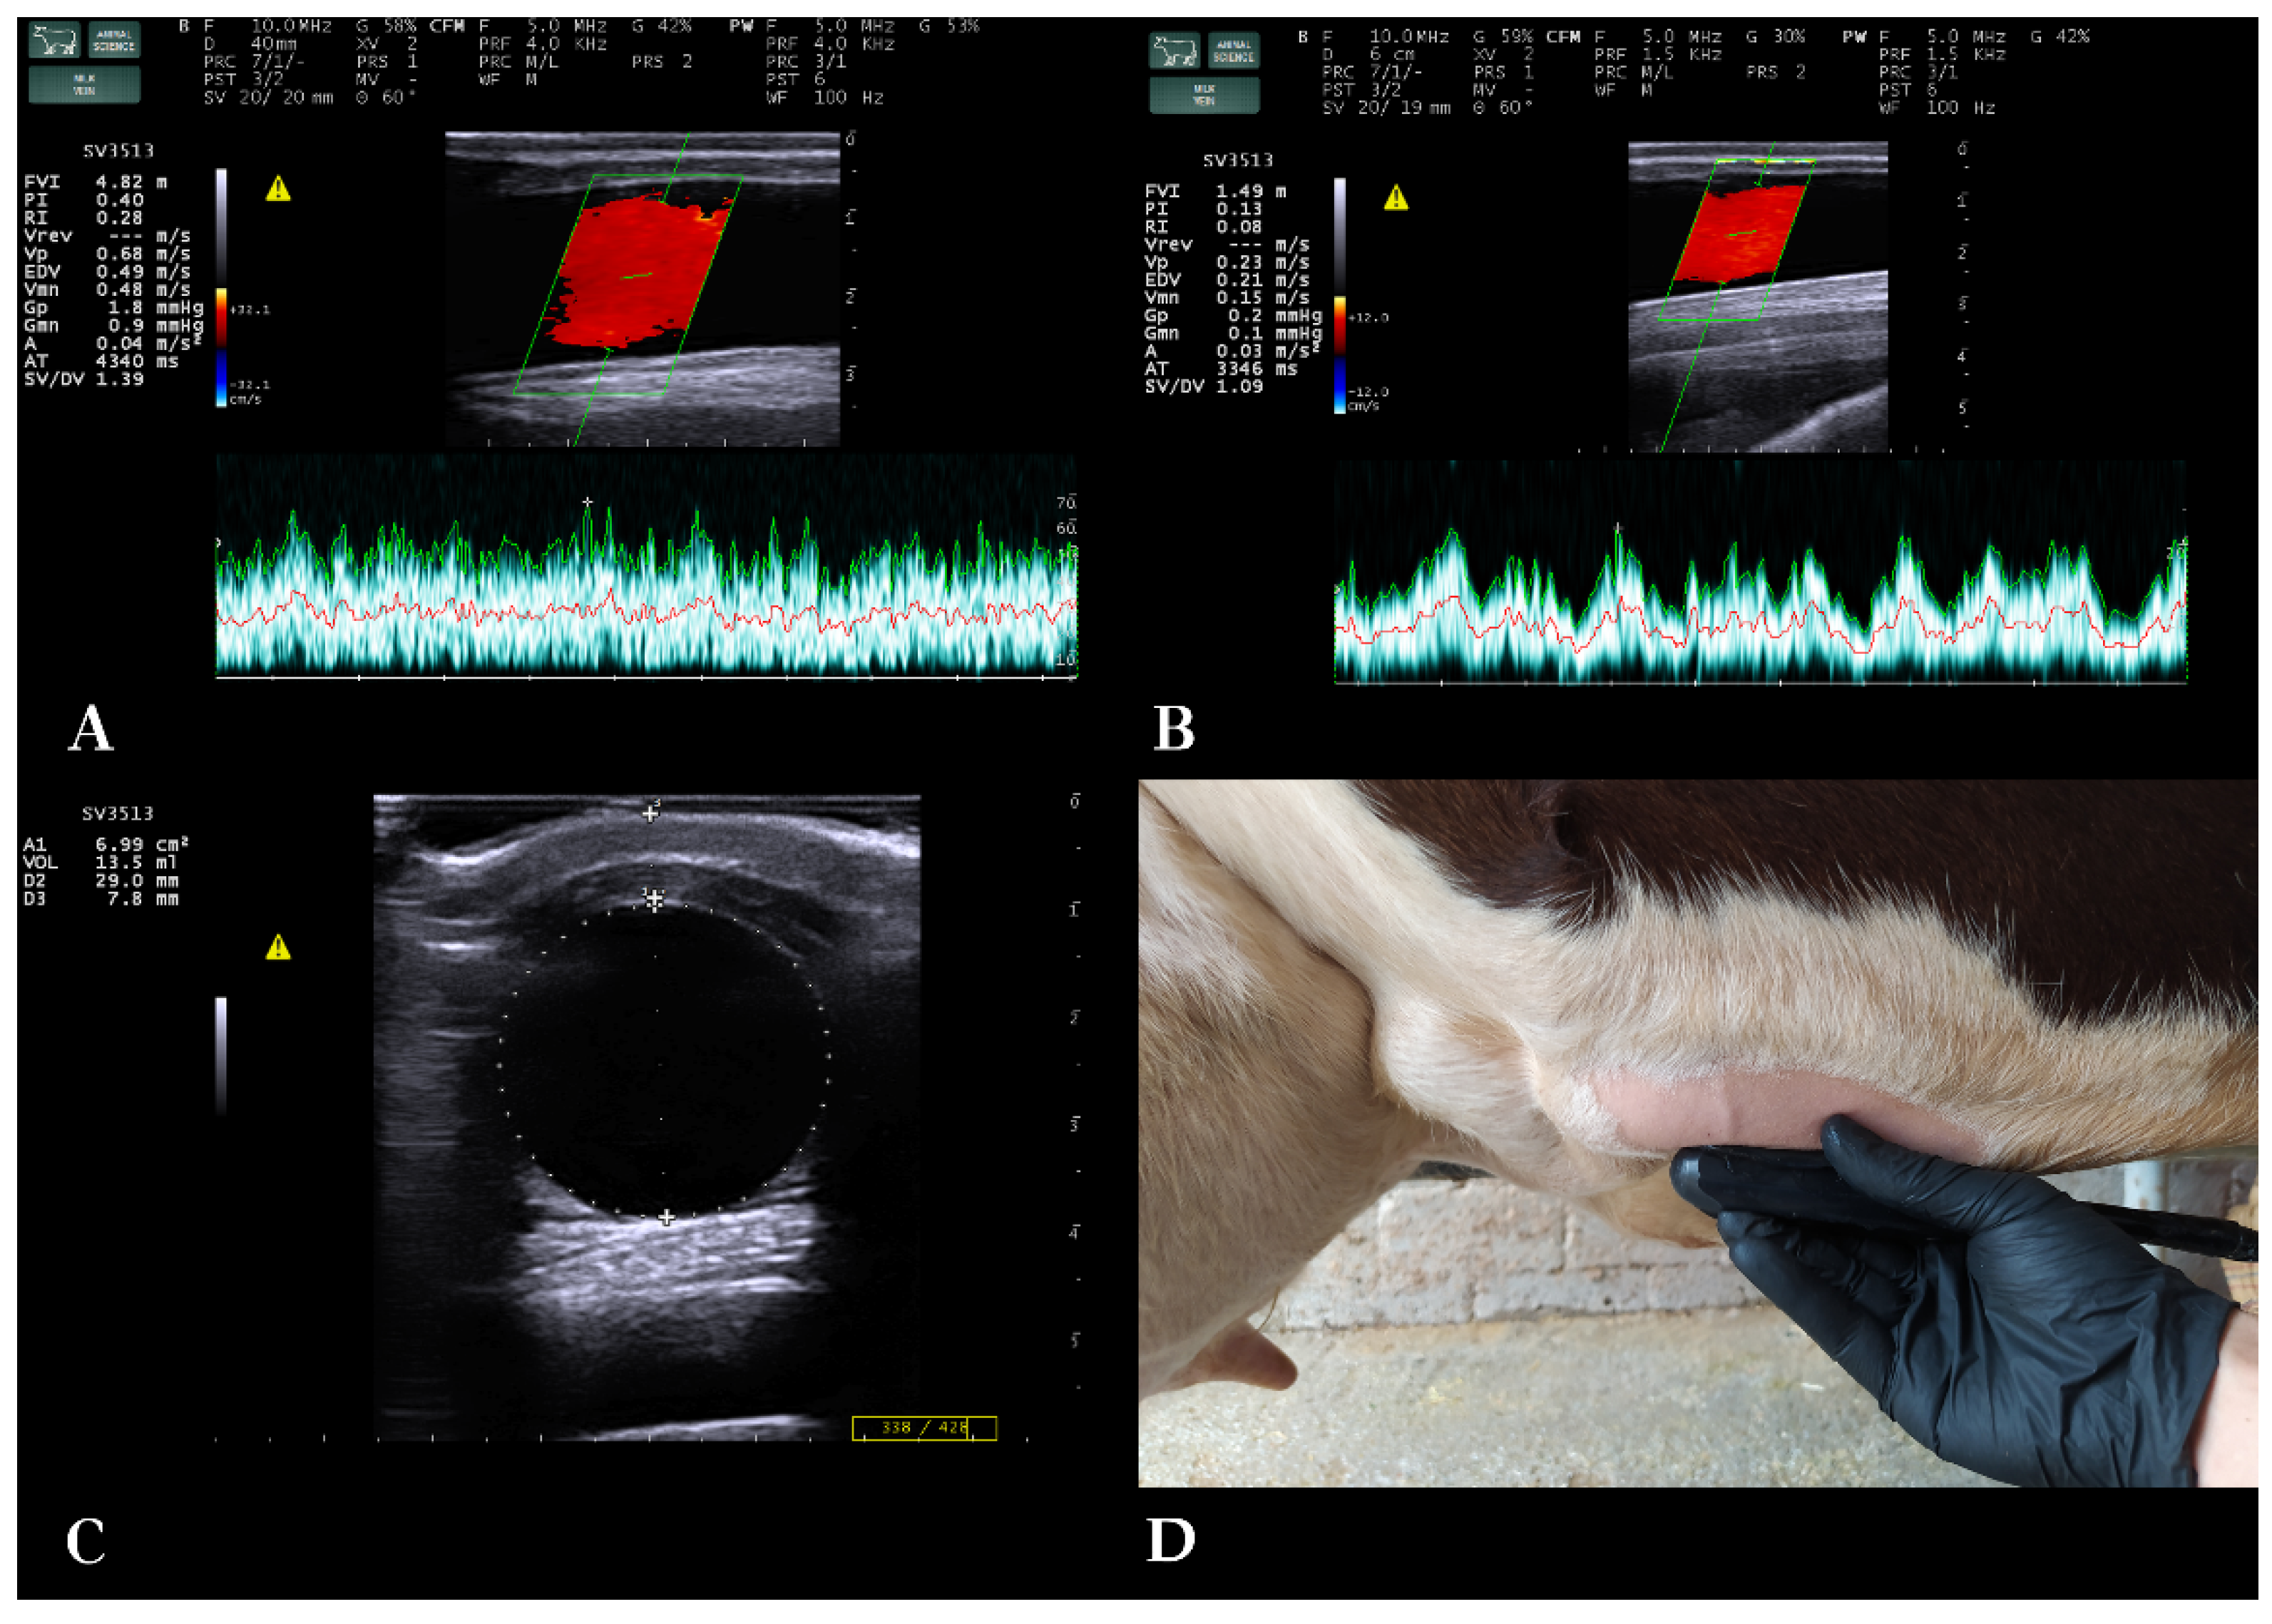

2.3. Ultrasonography of the milk vein (B-mode and spectral Doppler)

Cows were examined at standing position, non-sedated, restricted in a cattle crush, handled gently to minimize stress. Ultrasonographic examination of all cows was performed constantly by the first author. Morphology and blood flow of the milk veins were examined bilaterally with B-mode and spectral Doppler (triplex) ultrasonography, respectively. Cows had normal resting heart rate during the vascular flow examination [29]. The same ultrasound scanner was used, equipped with a broad-bandwidth multi-frequency linear transducer (SV3513, Esaote S.p.A., Genoa, Italy; 2.5–10 MHz). B-mode frequency was 10 MHz, scanning depth was 4–6 cm, gain 58% and time-gain compensation in neutral position.

A straight part of the milk vein was selected for the measurement located at the midpoint between its cranial and caudal part. The area was shaved, washed, degreased with 70% alcohol and covered with coupling gel (Figure 1). To avoid compression of the vein while ensuring sufficient contact, an appropriate amount of coupling gel was applied on the transducer, without the latter directly touching the skin. First, the transducer was positioned in cross-section to the vein. Distance of the milk vein from skin surface (D1) (cm), its vertical diameter from intima to intima (D2) (cm) and vein area in cross-section (A) (cm2) were measured from B-mode images.

Then, the transducer was positioned longitudinally to the vein, and Color Doppler gate was activated and placed at the center of the milk vein. Blood flow sample volume cursor included at least 2/3rds of the vein diameter, 16-20 mm wide, and theta angle was 60o (Figure 1). Blood flow was examined for 2 minutes per vein and 5 optimal spectral Doppler images were obtained from each milk vein measurement for further processing with MyLab™_Desk v. 9.0 software (Esaote S.p.A., Genoa, Italy). Blood flow parameters used were time-averaged mean velocity (TAMV) (cm/s), peak velocity (Vpeak) (cm/s) and milk vein blood flow volume (BFVol) (L/min) [23]. The total number of spectral Doppler sonograms used was 690 [345 measurement days * 2 milk veins (right/left) per cow].

A significant change was observed in the values of blood flow variables (BFVol, TAMV and Vmax) of the milk vein between late lactation, dry period and early lactation (Table 1, Figure 3). The highest value of mean BFVol was recorded at calving day, at 7.57±2.18 L/min and the lowest at mid-DP (21st day in the DP). The most abrupt changes in BFVol were observed between measurements “dry-off day” and “3rd day in DP” (decrease) and between measurements “3 days before calving” and “calving” (increase). TAMV and Vmax followed the same trend as BFVol throughout the study period.

Venous morphological parameters remained constant throughout late lactation, dry period and early lactation stage, despite significant changes in BFVol (Table 1). Change in BFVol is related to milk synthesis taking place in the mammary gland during late and early lactation, respectively. Indeed, in our linear mixed model BFVol appeared significantly associated both with DMY and production stage (Table 2). This is also apparent in the change of BFVol and DMY in time, as BFVol follows the curve of milk production: a rapid decrease within 3 days after the abrupt dry-off, followed by a stationary (non-lactating) period and then a rapid increase in BFVol one week before calving (Figure 3), when parenchymal re-growth and milk synthesis take place. Given the calculation formula BFVol = TAMV × 60 × A [18], the increased blood supply during lactation was achieved by increased flow velocities (TAMV, Vmax), while venous diameter and cross-sectional area remained constant. This explains why BFVol, TAMV and Vmax curves throughout the study period presented almost identical trends.

Figure 1. Spectral Doppler examination of the blood flow in the milk vein. A. Measurement of the blood flow features of a dairy cow’s milk vein on the 14th day in lactation, B. Measurement of the blood flow features of a dairy cow’s milk vein on the 35th day in the dry period, C: Measurement of the distance from skin surface, diameter and cross-sectional area of the milk vein, D. Placement of the probe for Doppler measurement of blood flow.